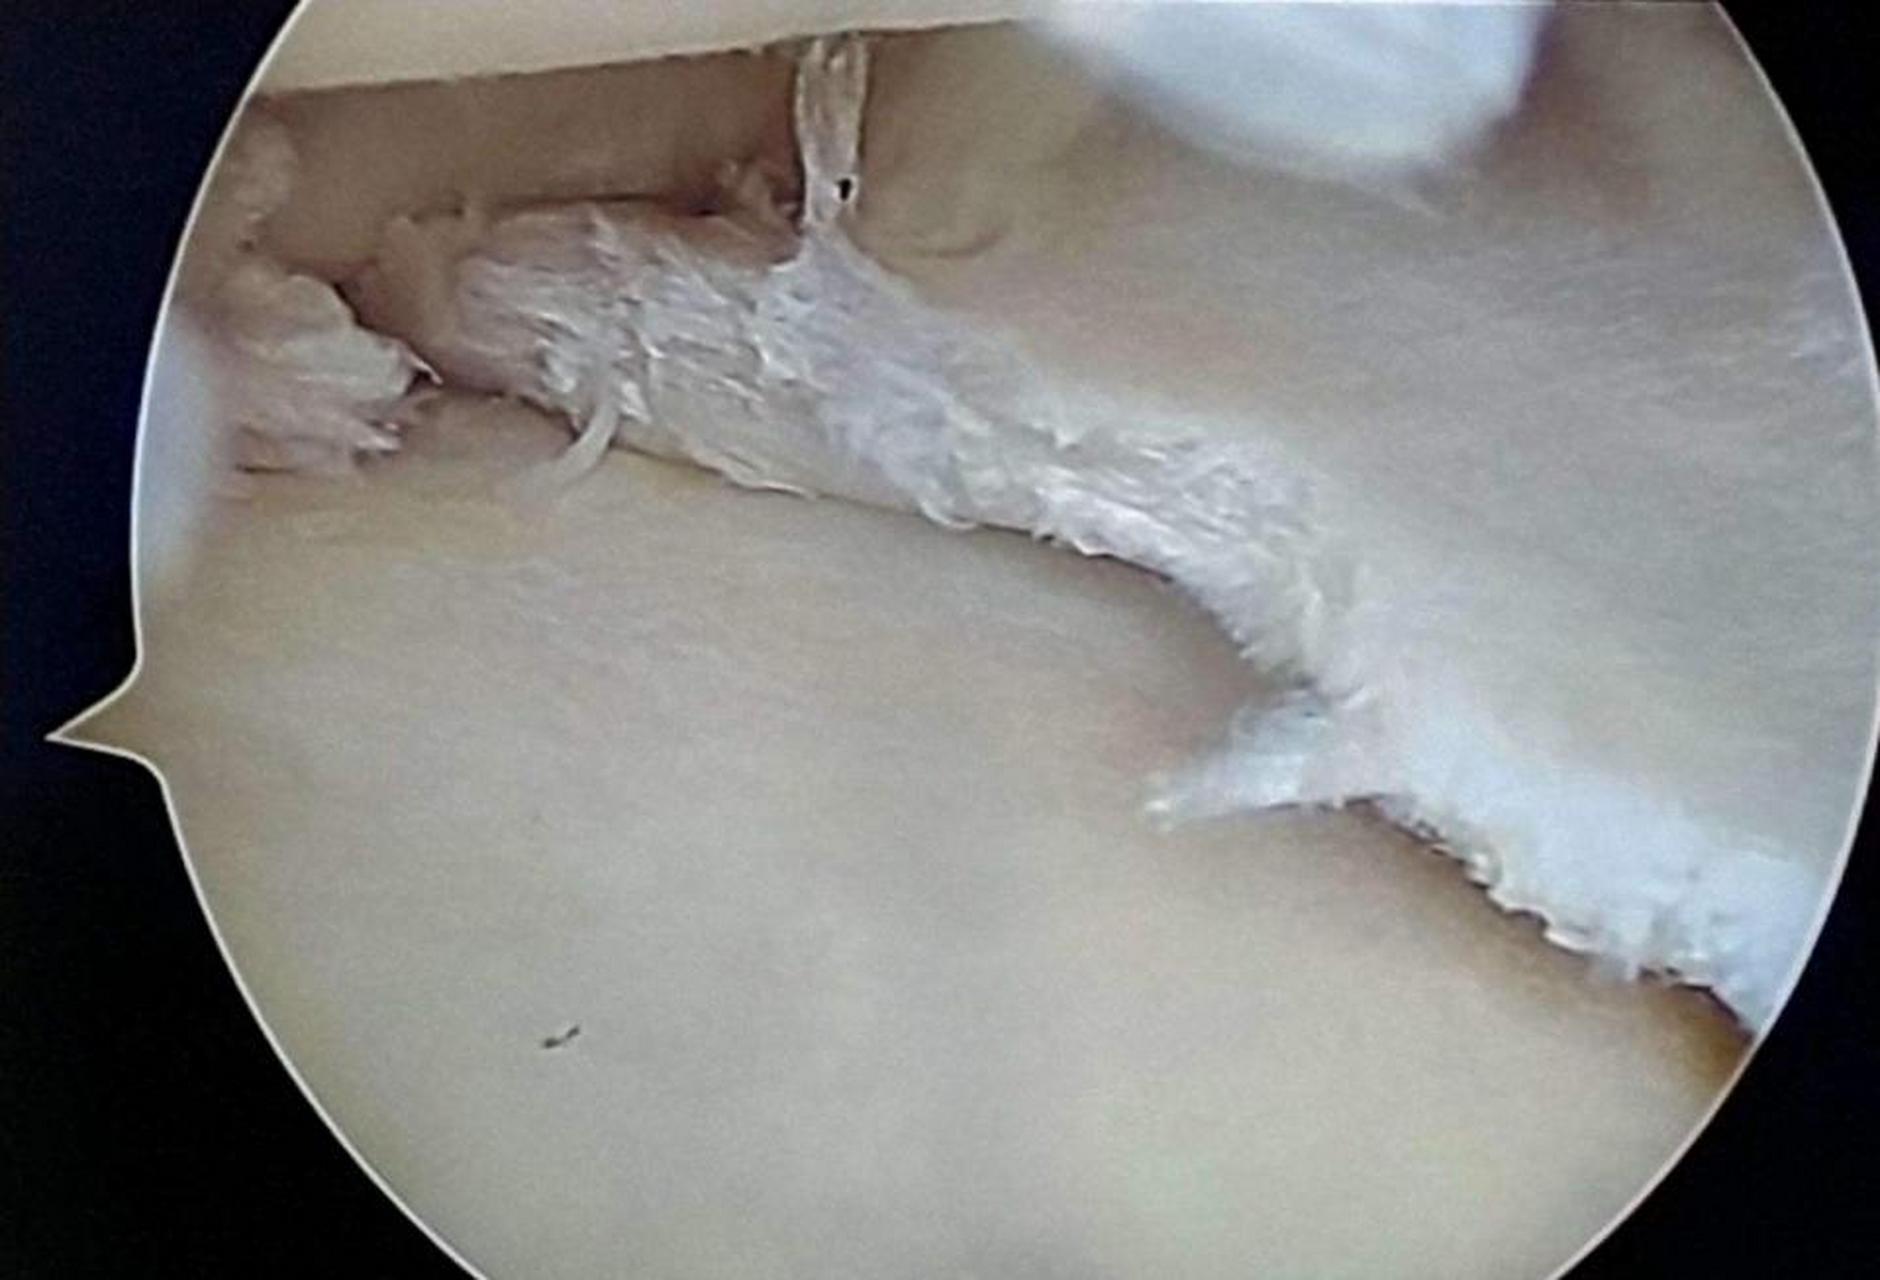

半月板撕裂最常见的症状是膝关节疼痛,关节肿胀,关节积液和活动受限